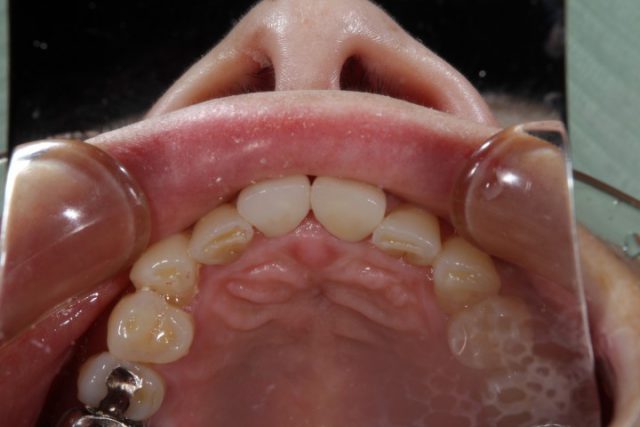

施術前